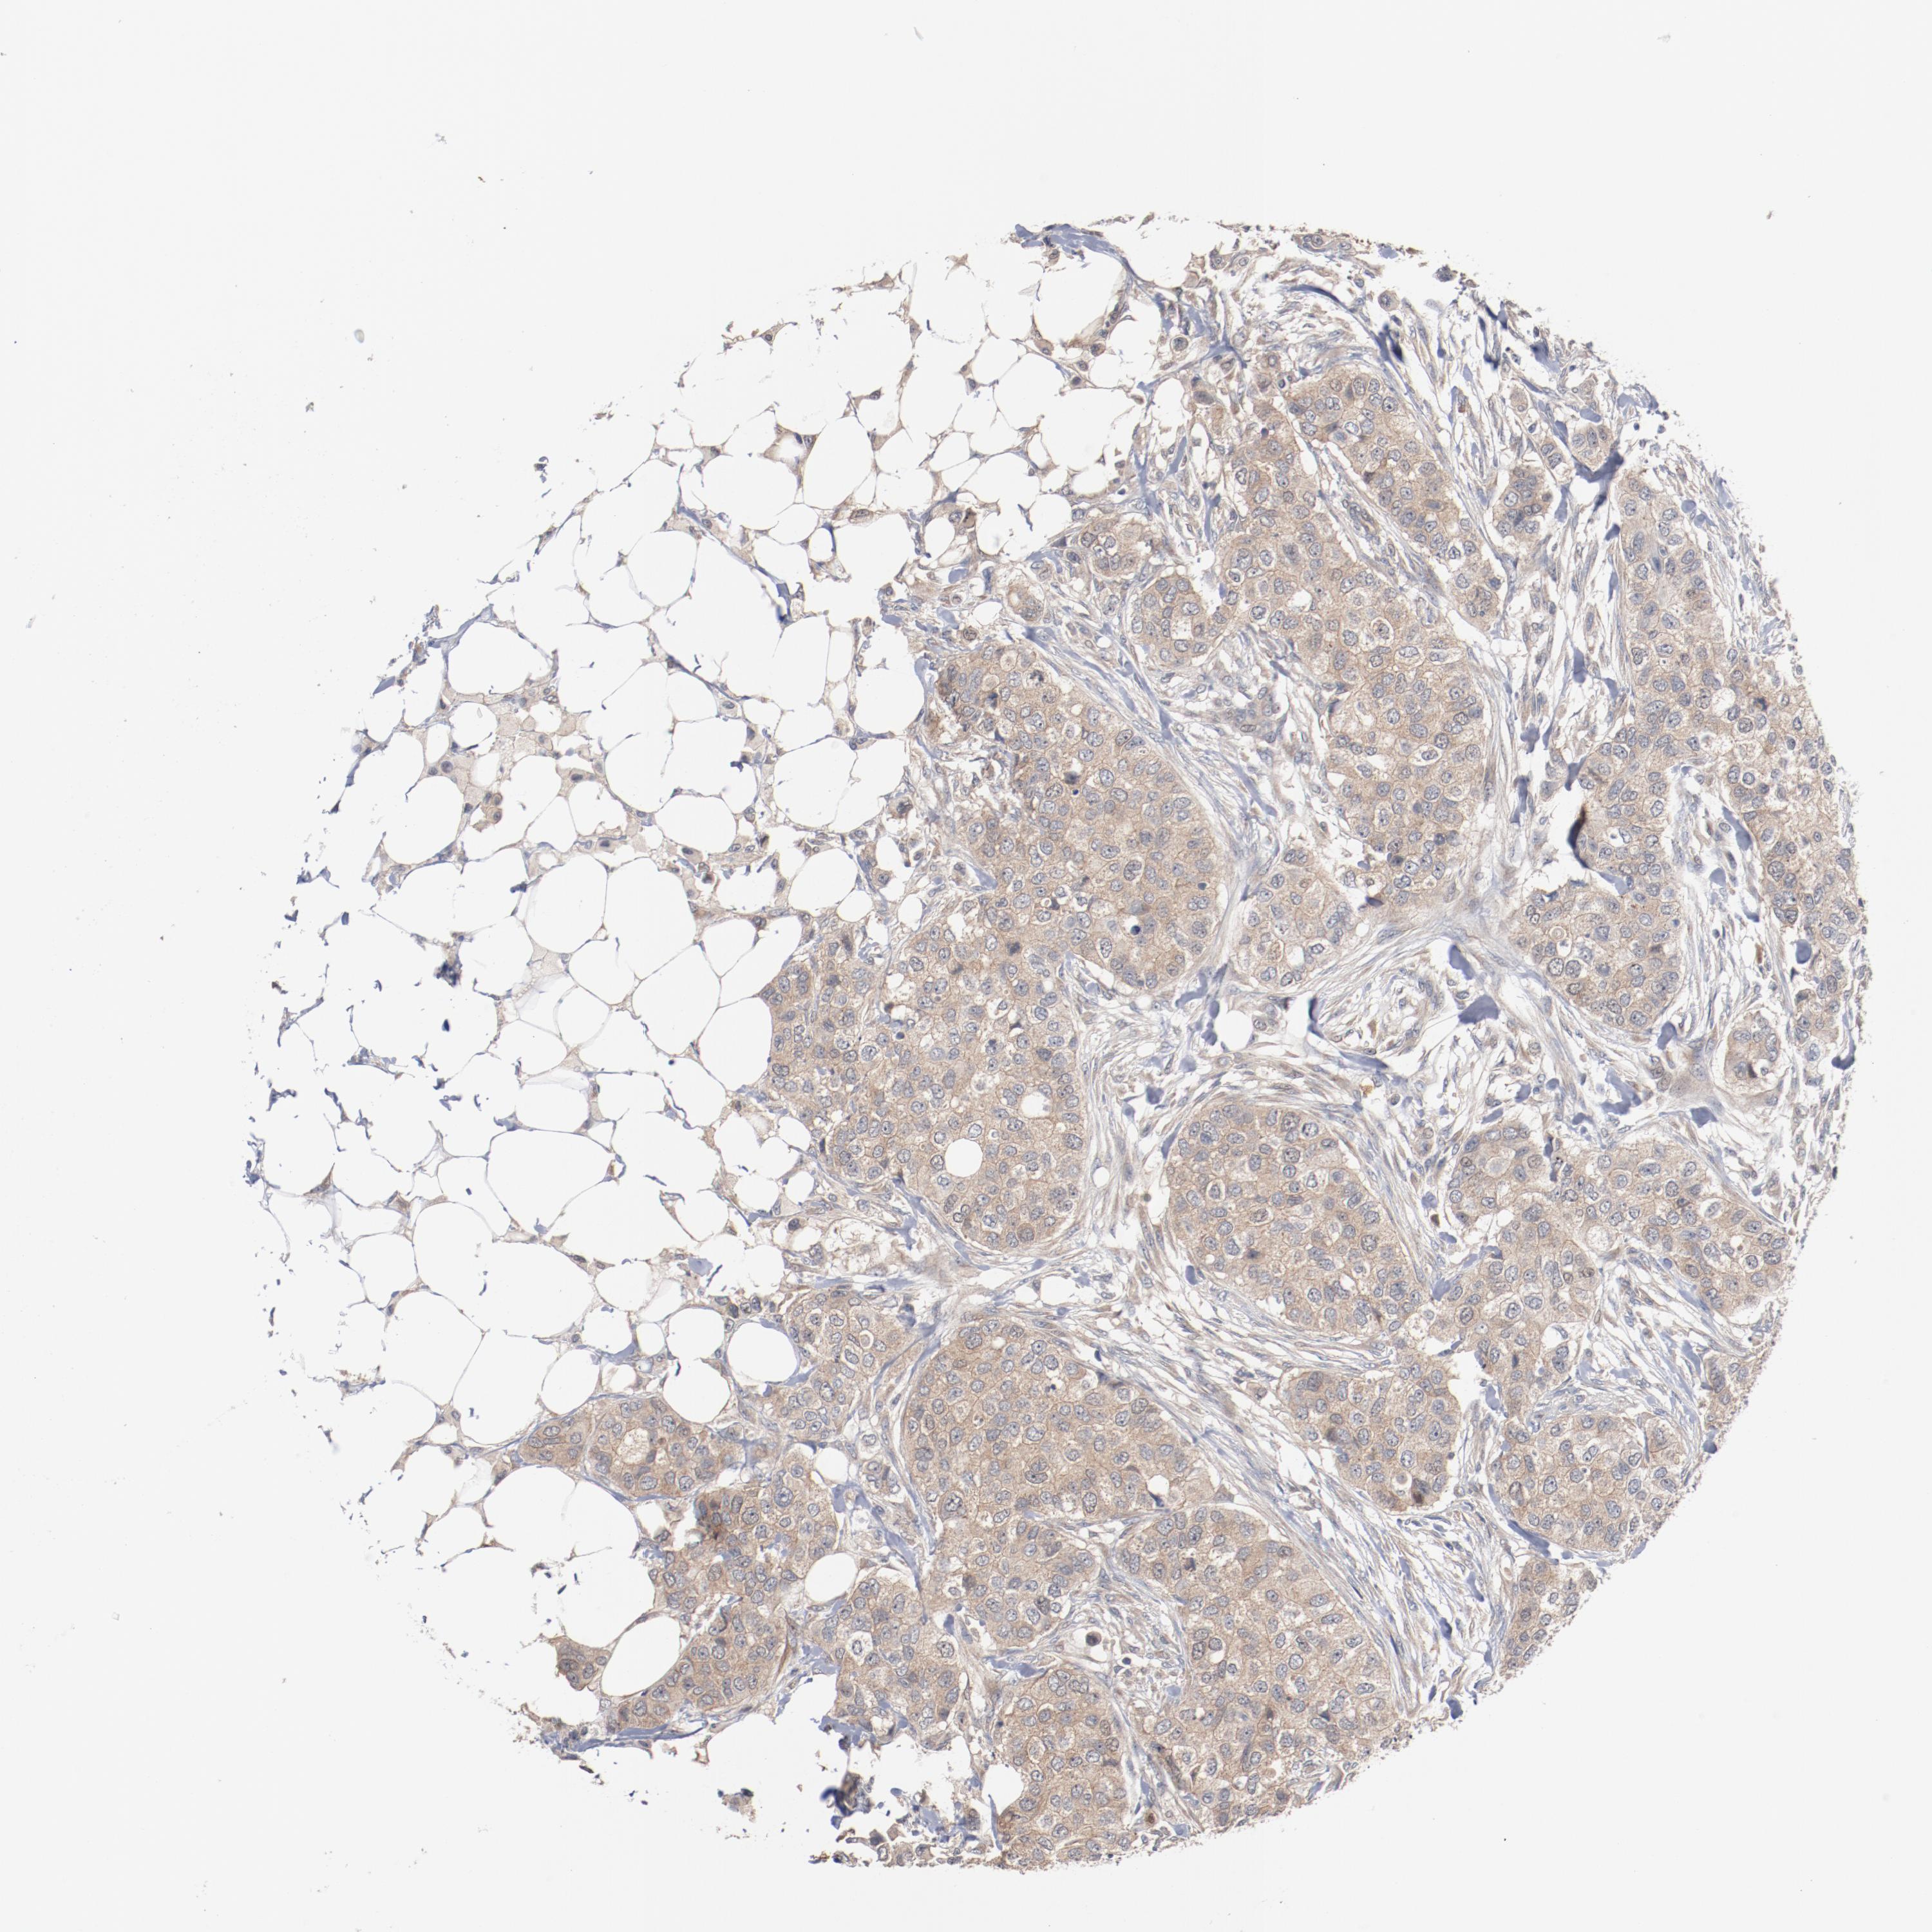

CANCER BREAST CANCER Show tissue menu

Breast cancer

Human cancer